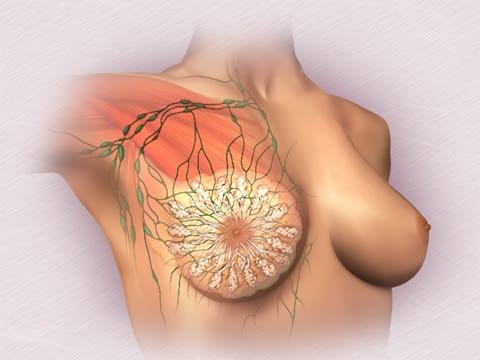

breast Breast mainly from the gland body,

pipe, fat organization and the fiber organize etc. composing.It is internal

structure a like small tree which pours a growth. The breast gland body constitutes

to°from 15~20 gland leafs, each gland leaf is divided into some leafs with

little gland, and each leaf with little gland constitutes to°from 10~100

gland bubbles again.These glands steep to closely arrange in the small milk

tube Surroundings, gland bubble of openings and small milk tube connect with

each other.Many small milk tubes gather together into a little milk tube

among the leafs, Many little milk tubes among the leafs gather together into

a whole gland the mammary glands pipe of the leaf further again, again lose a

milk tube. Lose a milk tube total 15~20, take nipple as center to present to

project form alignment, gather together dizzy open mouth at the nipple at the

milk, lose the milk bore at be called.

breast Breast mainly from the gland body,

pipe, fat organization and the fiber organize etc. composing.It is internal

structure a like small tree which pours a growth. The breast gland body constitutes

to°from 15~20 gland leafs, each gland leaf is divided into some leafs with

little gland, and each leaf with little gland constitutes to°from 10~100

gland bubbles again.These glands steep to closely arrange in the small milk

tube Surroundings, gland bubble of openings and small milk tube connect with

each other.Many small milk tubes gather together into a little milk tube

among the leafs, Many little milk tubes among the leafs gather together into

a whole gland the mammary glands pipe of the leaf further again, again lose a

milk tube. Lose a milk tube total 15~20, take nipple as center to present to

project form alignment, gather together dizzy open mouth at the nipple at the

milk, lose the milk bore at be called. Lose

a milk tube more narrow in the nipple, after it the Peng is greatly a pot of

stomach, lose the milk tube Dou at be called, there is the function of

storage human milk.Mammary glands pipe openings for reply the 1 F scale form

top skin cell, In order to move a form a top skin narrow place, the pot all

levels pipe with following stomach is a pair of layers pillars form top skin

or single layer pillar form top skin, eventually the end pipe near gland

bubble in order to sign square and last skin, the gland bubble inner pad

signs square and last skin. |